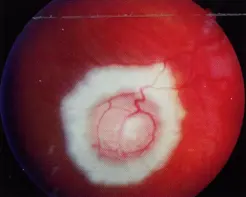

Right After Laser Photocoagulation

6 Months After Photocoagulation

RB

After plate radiation therapy